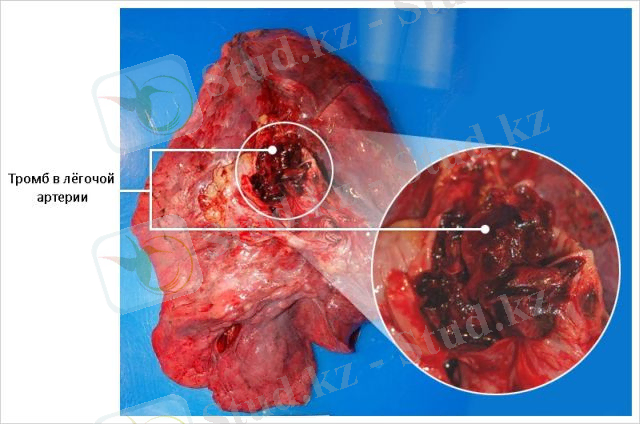

6. Тромбоэмболияның өкпелік артериялары (TELA) - қан тамыры арқылы филиалдардың немесе өкпе артерияларының кенеттен құлауы (эмболус), жүректің оң жақ қарыншаында немесе атриумында пайда болады, қан айналымының үлкен шеңберінің веноздық қабаты және қан ағымымен бірге әкелінеді.

Өкпе артериясының тромбоэмболиясы (ӨАТЭ) - қан тамыры арқылы филиалдардың немесе өкпе артерияларының кенеттен құлауы (эмболус), жүректің оң жақ қарыншаында немесе атриумында пайда болады, қан айналымының үлкен шеңберінің веноздық қабаты және қан ағымымен бірге әкелінеді. Өкпелік тромбоэмболияның нәтижесінде өкпе тініне қан беру тоқтатылады. Өкпелік тромбоэмболияның дамуы жиі болып тұрады және науқастың қайтыс болуына әкелуі мүмкін.

- ангиопульмонография (қан ұйығышының орналасуын және өлшемін дәл анықтау үшін)